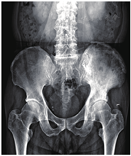

Paget′s骨病是一种成人的慢性骨骼疾病,55岁以上人群多见,西欧、北美等地区的人群发病率高于亚洲人群。Paget′s骨病的特征为局部骨转化增加,正常的基质被软化和增大的骨性结构所取代,常见于骨盆(70.0%)、股骨(55%)、腰椎(53%)、颅骨(42%)和胫骨(32%)[8]。Paget′s骨病患者可无症状,并在影像学检查中偶然发现,部分患者可有骨痛或伴局部皮温增高及压痛。患者的血清碱性磷酸酶通常增高,且由于破骨细胞异常、骨强度降低,可以发生骨折、畸形[8]。如前所述,PSMA在Paget′s骨病中可有阳性摄取,可能与骨重塑和新生血管增加有关[9],所以本例68Ga-PSMA-11 PET/CT的表现也支持Paget′s骨病的诊断。患者2016年11月行左侧髂骨活检,病理未见肿瘤,血清碱性磷酸酶222(正常参考值范围:45~125) U/L,骨盆正位X线片提示左侧髂骨大片骨质密度增高影(图2),符合Paget′s骨病诊断。患者后于本院门诊规律随诊至2023年6月,临床诊断为前列腺增生。